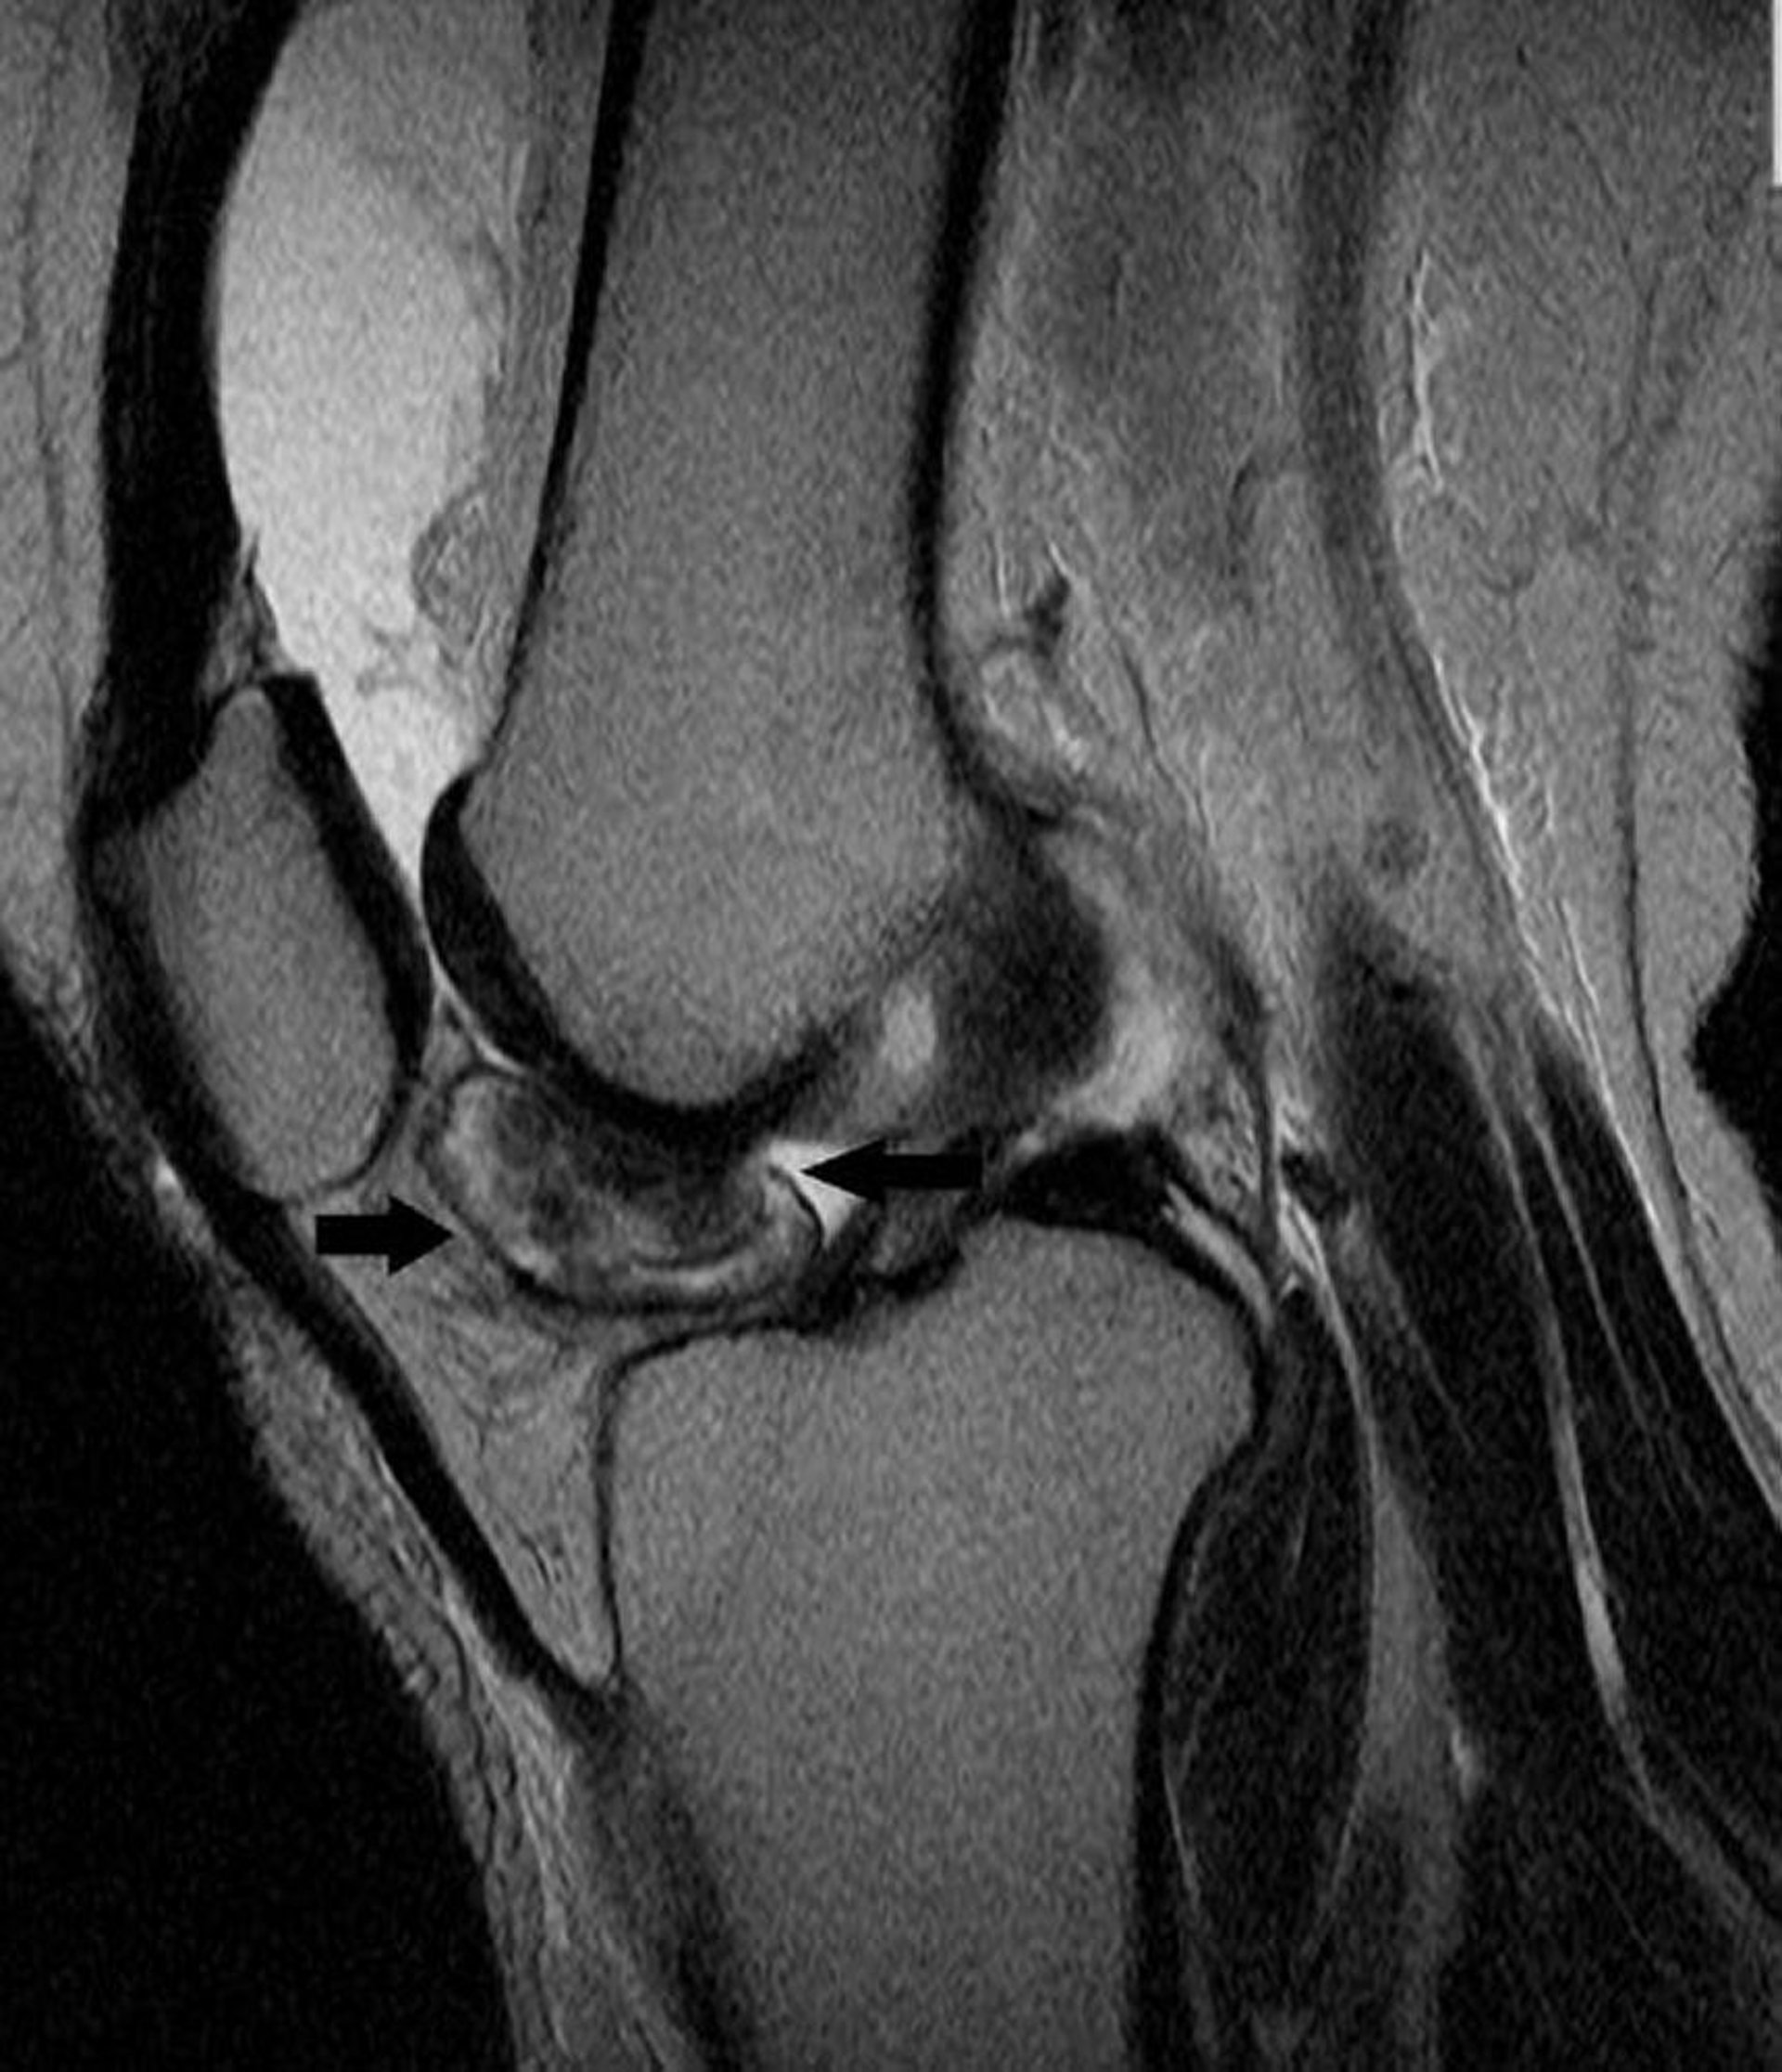

Tumeur ténosynoviale à cellules géantes

Cette IRM du genou montre une tumeur à cellules géantes ténosynoviales dans la paroi de l'articulation du genou (flèches).

Image courtoisie de Michael J. Joyce, MD, and Hakan Ilaslan, MD.